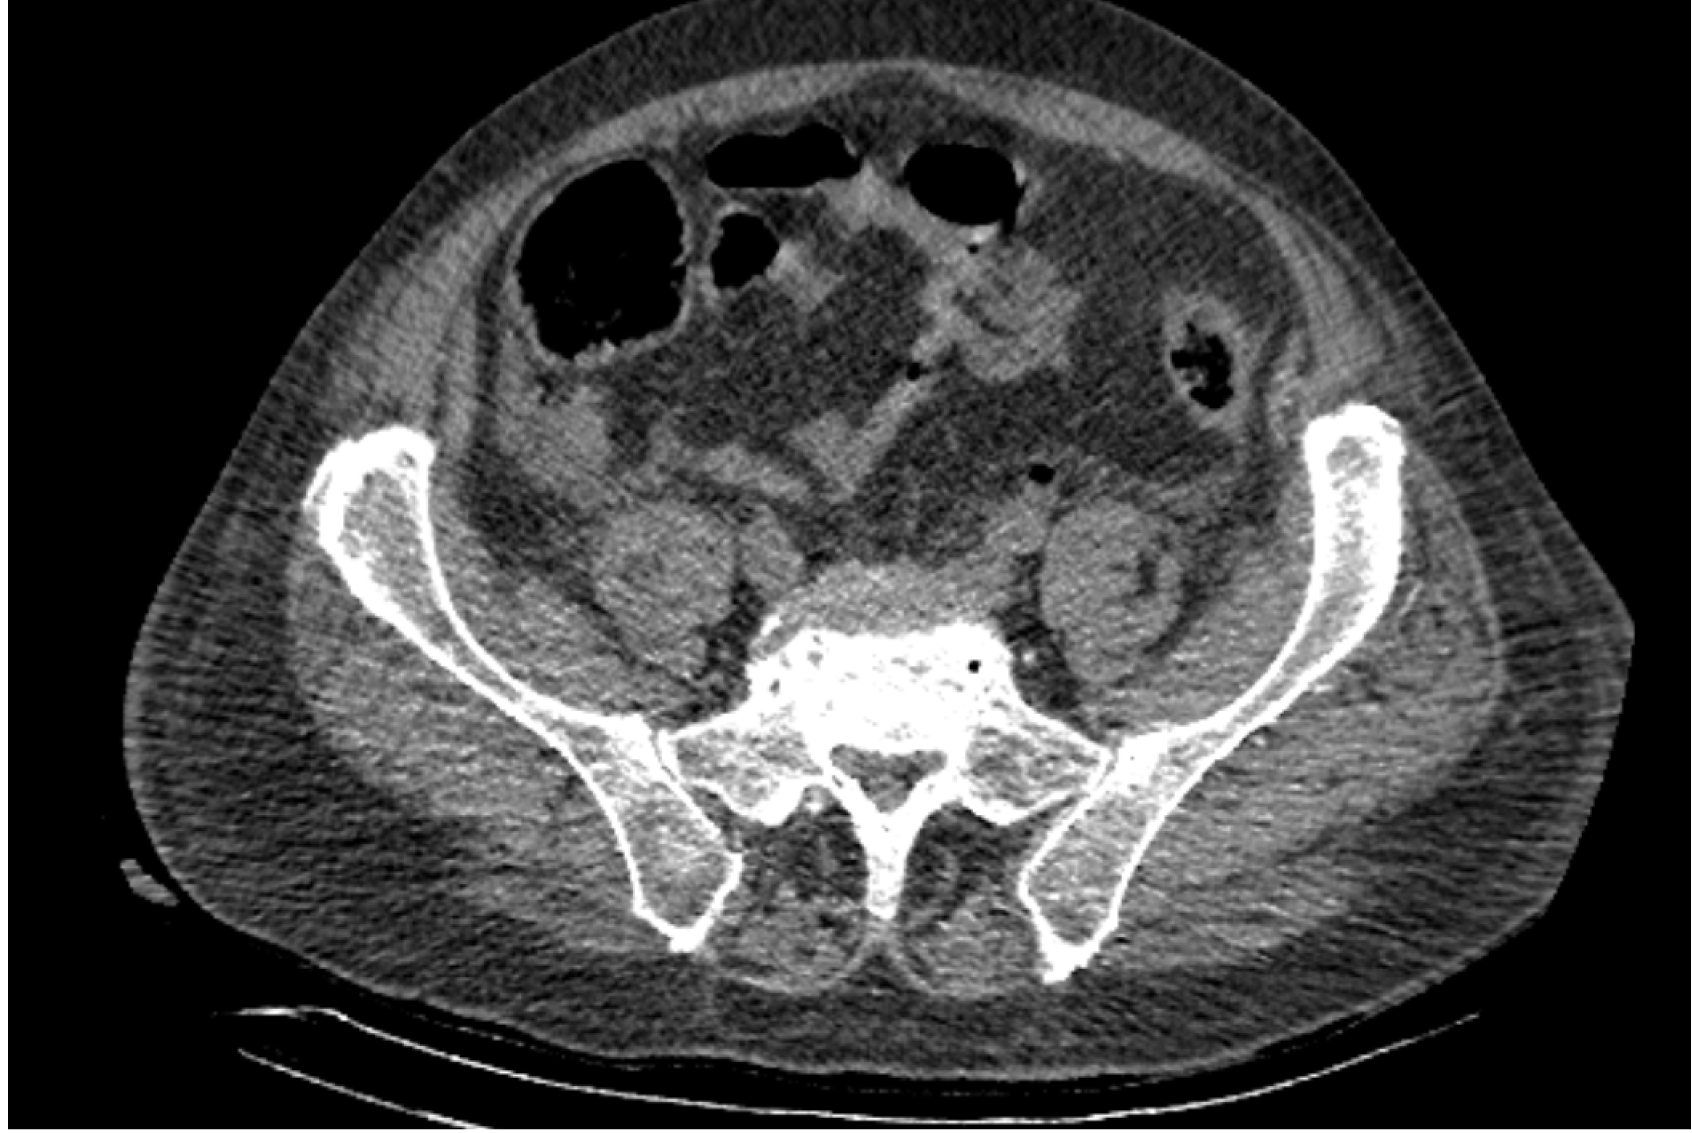

На следующий день состояние пациента оставалось тяжелым, с отрицательной динамикой, креатинин сыворотки возрос до 735,2 ммоль/л, Появились жалобы на слабость, тошноту. При осмотре: живот мягкий, вздут по всем отделам, при пальпации болезненный. Область почек не изменена, при пальпации безболезненна, патологических изменений в области почек не выявлено. Симптом поколачивания отрицательный билатерально. При УЗИ были обнаружены плевральный выпот по 300–400 мл с каждой стороны, гепатомегалия, увеличение размеров селезенки, асцит. Кроме того, в обеих почках были визуализированы тени, характерные для конкрементов. По данным компьютерной томографии (КТ) конкрементов не обнаружено, но в лоханке, на всем протяжении левого мочеточника и, частично, в правом мочеточнике, а также в мочевом пузыре визуализировался газ (рис. 1–6).

Рис. 3. Компьютерная томография органов брюшной полости, забрюшинного пространства, органов малого таза. Газ в левом мочеточнике